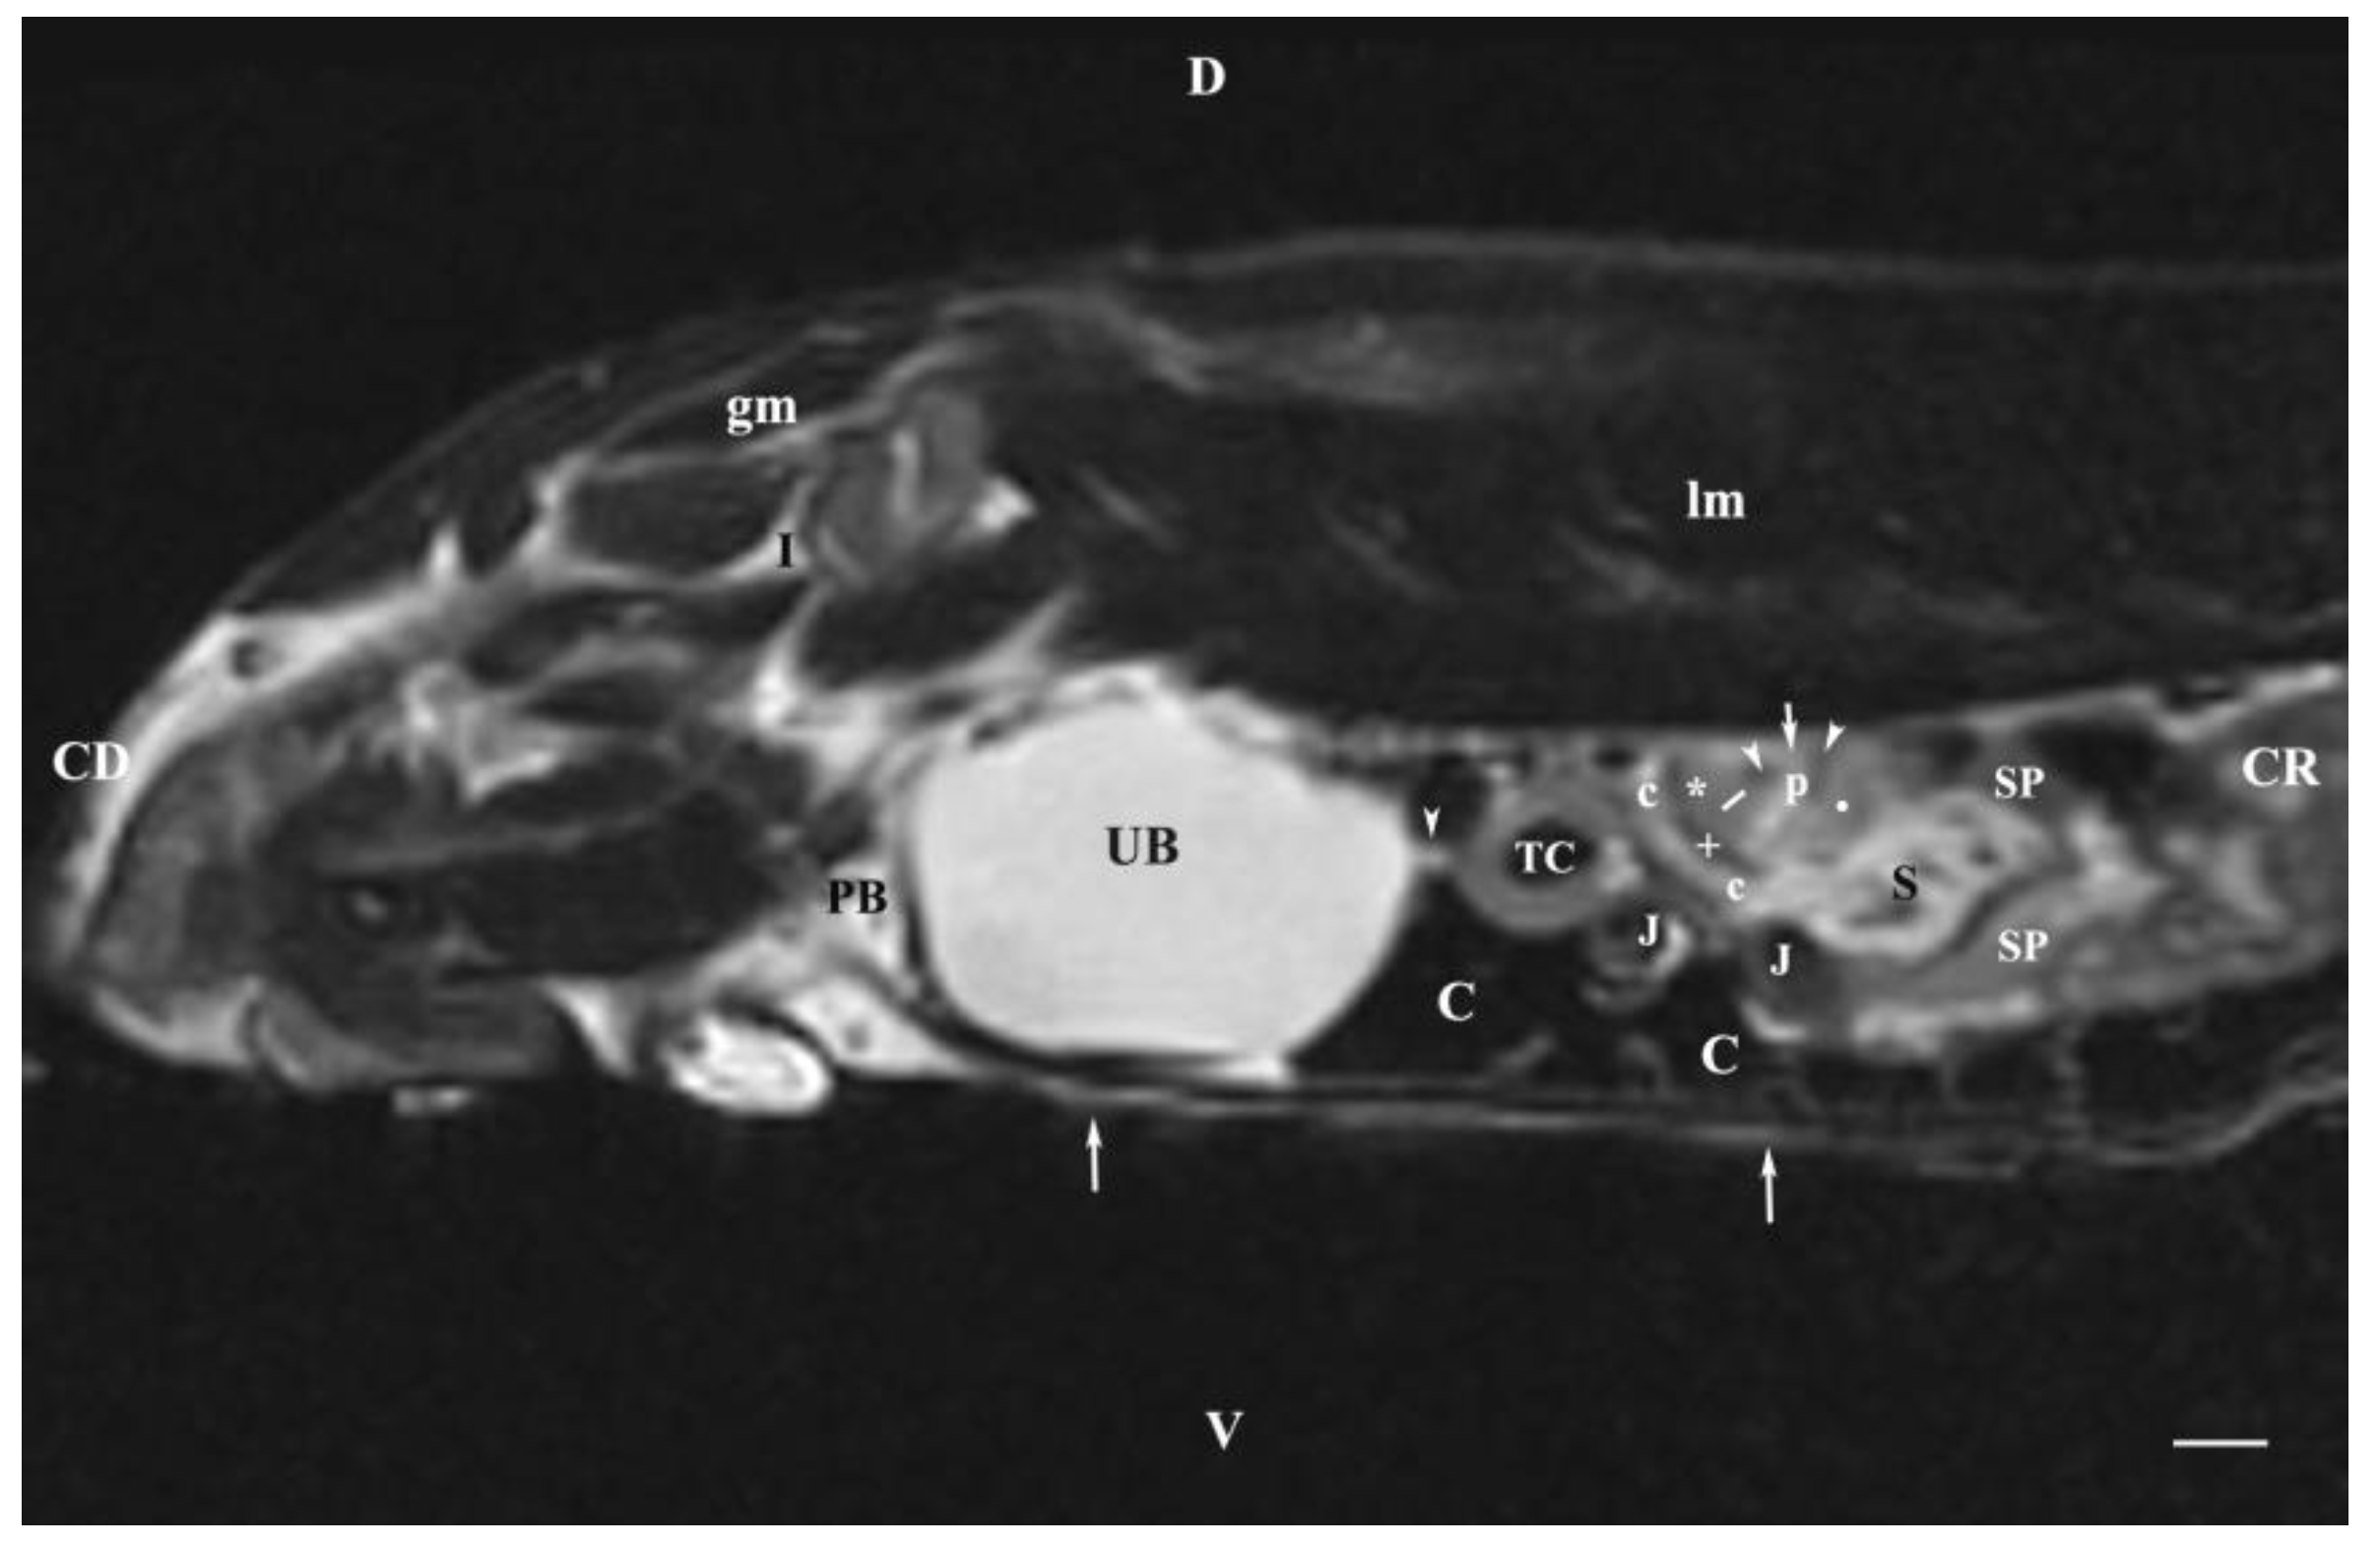

Sagittal T2-weighted image of the abdominal cavity 30 mm to the right of the median plane showed the almost entire right kidney (in the dorsal lumbar area) and the right ureter and the urinary bladder as well. The right kidney demonstrated its specific bean shape, and the renal hilus was seen as a hypo intense dorsomedially located structure. The renal pelvis was clearly outlined as a hyper intense finding of irregular borders. Peripherally to it, the hypo intense dorsal and ventral recesses were visualized. The corticomedullary definition was clearly demarcated as an intense irregular finding of transient intensity, situated between the hyper intense medulla and the relatively hypo intense cortex. The renal adipose capsule was hyper intense and the fibrous capsule—hypo intense. The craniolateral border of the right kidney touched the heterogeneous hypo signal liver. The inner and outer areas of the kidney medulla were not distinguished. Caudoventrally to the hyper intense adipose capsule of the right kidney appeared the hyper intense tubular right ureter whose lumen was more intense than its walls. The hyper intense signal of the urinary bladder body was observed in the caudal abdomen, clearly delineated from the adjacent soft tissues. The latter comprised the heterogeneous images with varying signal intensity of the transverse colon, the transverse duodenum, the caecum, the jejunum and the mesentery. The urinary bladder neck was not observed (Figure 7).

The sagittal T2-weighted MRI (30 mm lateral and right to the median plane) demonstrated only the image of the right kidney, due to the relatively close location of the right kidney to the median plane compared to that of the left kidney, which remained more aside. The image of the right kidney was completely defined and informative, and its different parts showed a various degree of heterogeneity and intensity. The image of the right ureter was caudal to the caudal end of the right kidney, with hyper intense signal characteristics without clear distinction between the lumen and the ureteral walls. Therefore, the right ureter was not filled with urine at the time of MR scanning due to the caudal tissue motility wave that moved urine towards the urinary bladder. The difference in the intensity of the renal image (hypo intense) and the renal pelvis image (hyper intense) was due to the option of T2-weighted sequence—indicating fluid findings. The lack of urine in the renal sinus was the cause for the hypo intense signal. Compared to the transverse section, the different parts of the medulla on the sagittal one had no defined signal intensity. The renal cortex demonstrated a lower relative intensity with respect to the medulla on the sagittal section than on the transverse one. The homogeneous character of tissue intensity of the cortex was due to the difficult differentiation of its granulosa part. Opposing to the cortex, the medulla was heterogeneous and hyper intense because of the unclear distinction of its two areas and the increased degree of hydration. The kidney fibrous capsule and the renal sinus were the structures with the lowest image intensity, consequently to their low fluid content.

Figure 7. MRI imaging anatomy of organs from the middle abdominal region (sagittal section) (T2-weighted sequence 30 mm to the right of the median plane) (Right kidney). CD-caudal, CC-cranial, D-dorsal, V-ventral. (UB) urinary bladder; (p) renal pelvis; (black star) renal cortex; (white line) renal medulla; (black point) corticomedullary junction; (h) renal hilus; (white cross) fibrous capsule; (oblique white arrowhead) dorsal and ventral renal recess; (perpendicular black arrowhead) ureter; (S) stomach; (L) liver; (c) renal adipose capsule; (rm) mesenterial root; (J) jejunum; (TD) transverse duodenum; (TC) transverse colon; (C) caecum; (A) adipose tissue; (PB) pubic bone; (lm) longissimus muscle; (gm) gluteal muscles; (I) ilium (white perpendicular arrow) abdominal wall. Line=10mm.